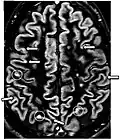

| Double inversion recovery | DIR | Simultaneous suppression of cerebrospinal fluid and white matter by two inversion times.[79] | High signal of multiple sclerosis plaques (pictured).[79] |

| |